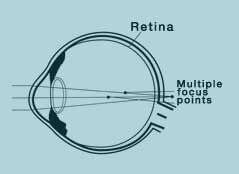

Astigmat (astigmatism)

Your vision is distorted when looking objects at a distance and objects that are close.

A natural spot looks like a line in your perception.

The reason is that the cornea layer has an elliptic egg like shape instead of a sphere. Here, the light beams are not collected on a single spot by being refracted differently; instead, they spread all over the retina.

Astigmatism is usually seen with myopia or hypermetropia and its correction value is shown in dioptres.

In the correction process, the top surface of the cornea is brought closer to a spherical shape in order to combine all light beams in a single spot. And laser balancing is applied by balancing vaulting in such a way to collect all light beams in a single focal point.